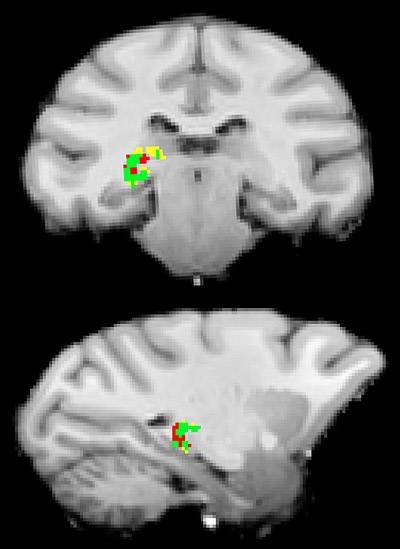

Princeton University researchers have found that the pulvinar, a mysterious region deep in the human brain, acts like a switchboard operator to make sure that separate areas of the brain are communicating about the same external information most important to our behavior at a given moment. The pulvinar uses electrical impulses to synchronize and allow more effective communication between brain cells in the visual cortex, which processes visual information. The researchers produced neural connection maps that show the pulvinar's connection to these brain regions. In this scan, the pulvinar communicates with the occipital lobe (yellow) and the temporal lobe (red) individually, and with both (green). Image courtesy of Science/AAAS

After producing neural connection maps, the researchers used electrodes (blue arrows and green crosshairs) to monitor the direct communication paths (yellow-orange) between the pulvinar and clusters of brain cells, which in this case are in the temporal lobe. Image courtesy of Science/AAAS